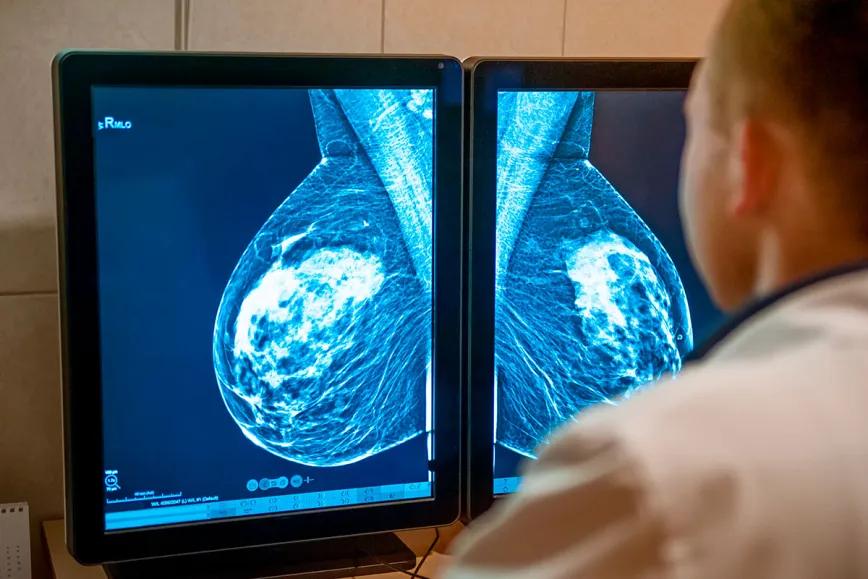

Un nuevo estudio realizado por universidades tailandesas encontró que el cannabidiol (CBD) puede ayudar a frenar el crecimiento de un tipo de cáncer de mama muy agresivo. Se trata de resultados preliminares en laboratorio, pero que apuntan a un posible papel del CBD en terapias futuras.

Publicado en el Journal of Cannabis Research, el estudio fue llevado a cabo por investigadores de las universidades Rangsit y Mahidol. En sus pruebas con células cancerosas en laboratorio, observaron que el CBD interfiere con una vía que favorece el crecimiento del tumor. El foco fue un subtipo conocido como cáncer de mama triple negativo, que suele ser más difícil de tratar porque no responde a terapias comunes.

Este tipo de cáncer no tiene los receptores hormonales que permiten aplicar tratamientos habituales, lo que lo hace más agresivo y propenso a reaparecer. Uno de los mecanismos que lo hace tan resistente es una proteína llamada EGFR y la investigación sugiere que el CBD podría frenar parte de su acción.